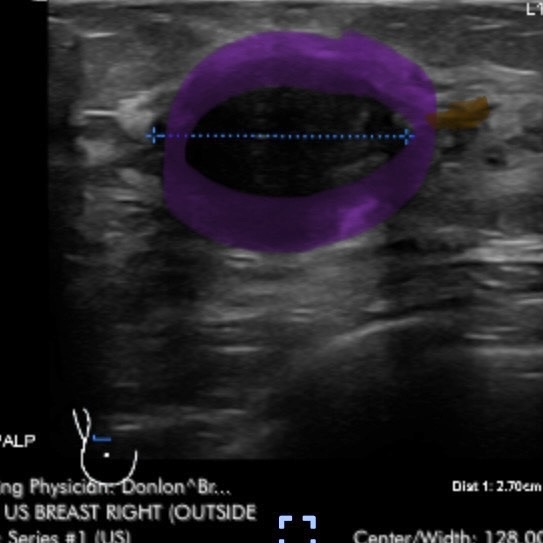

These doctors are so far my faves, but I have a total of 13 members on my care team. I met with all of them within a couple weeks. They first ordered a breast ultrasound, and a mammogram. The ultrasound confirmed the size of my tumor, 3cm or the size of a large grape.